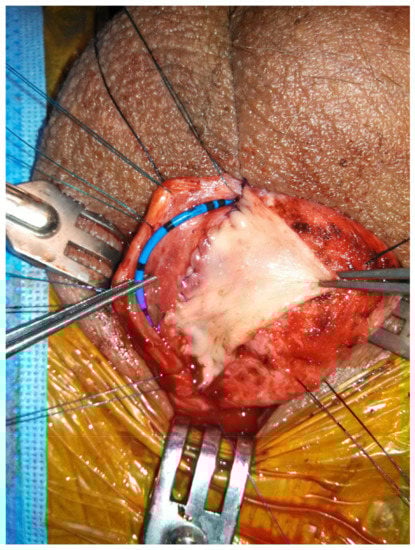

Figure 2. Non-transecting, dorsal onlay buccal mucosal graft urethroplasty.

When the bulbar stricture is long (>2 cm) and non-obliterative, a dorsal onlay urethroplasty can be performed. Initially described by Barbagli in 1996, the technique has been modified over the years and has been shown to have durable success rates [29]. Dorsal graft placement has the benefit of strong corporal fixation, thus reducing risk of sacculation (Figure 2). There is also less operative blood loss due to the thinner bulbospongiosus dorsally. Ventral onlay described by Morey and McAnnich is also an option with durable success [30]. This option is preferred by some when the exposure is challenging due to proximal stricture location or obesity.